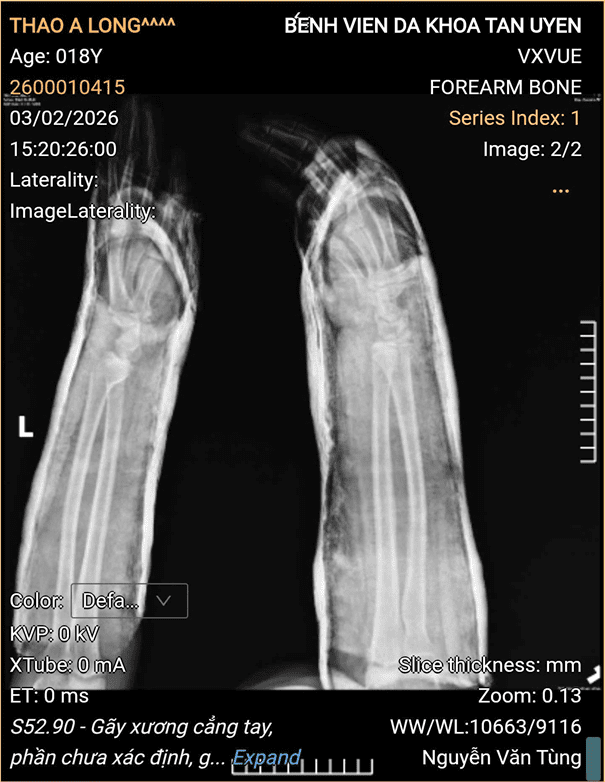

Đến ngày 03/02/2026, sau khi đánh giá toàn diện tình trạng tổn thương, các bác sĩ Bệnh viện Đa khoa Tân Uyên đã chỉ định kéo nắn, bó bột hai cẳng tay cho bệnh nhân. Quá trình thực hiện đảm bảo đúng kỹ thuật, kết quả kéo nắn tốt, ổ gãy vững, bệnh nhân đáp ứng điều trị tích cực. Sau thời gian theo dõi hậu thủ thuật, tình trạng bệnh nhân ổn định, được cho ra viện sớm, tiếp tục theo dõi và tái khám theo lịch hẹn.

Hình ảnh của bệnh nhân và Bác sĩ Khoa Ngoại:

Hình ảnh của bệnh nhân trước khi kéo nắn.